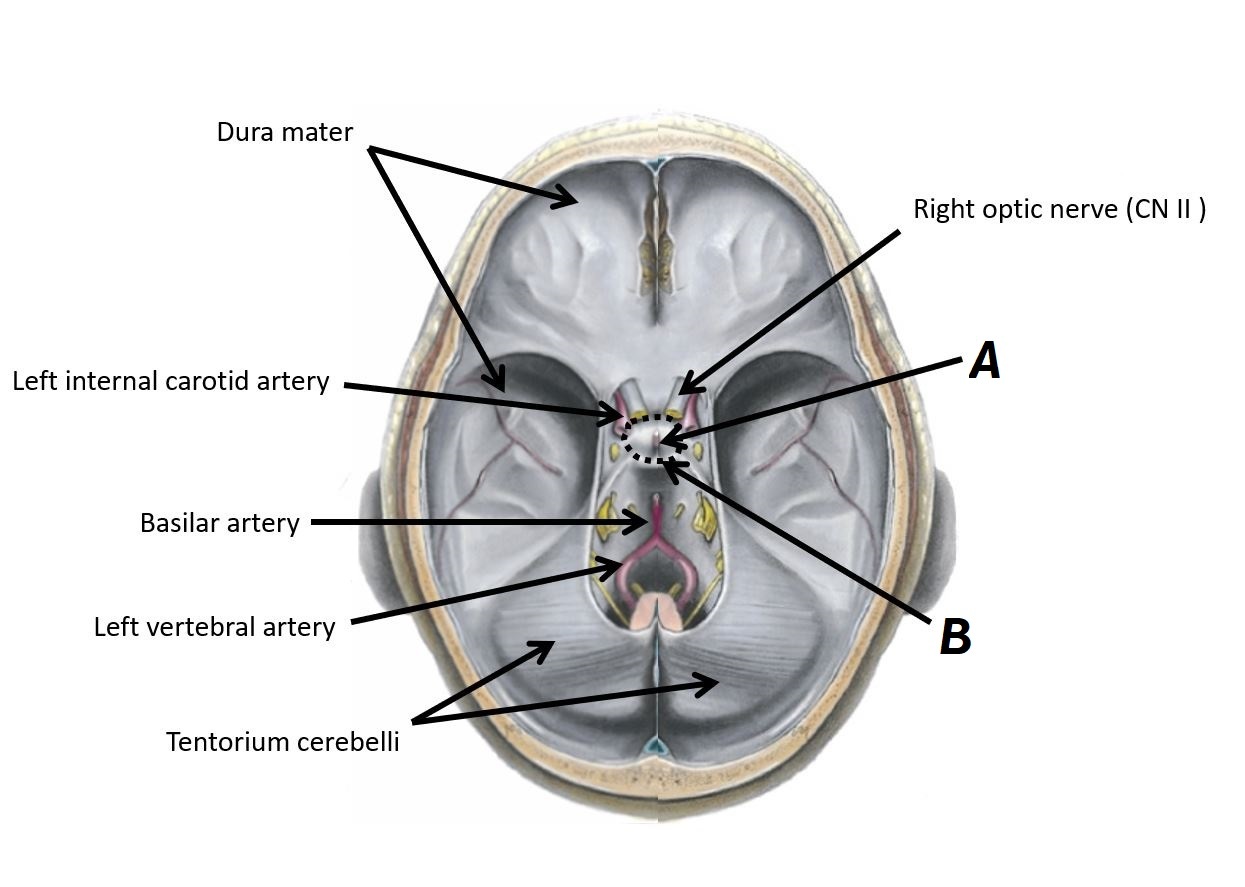

Name structures A, B and C

A - Left internal carotid artery

B - Basilar artery

C - Left vertebral artery